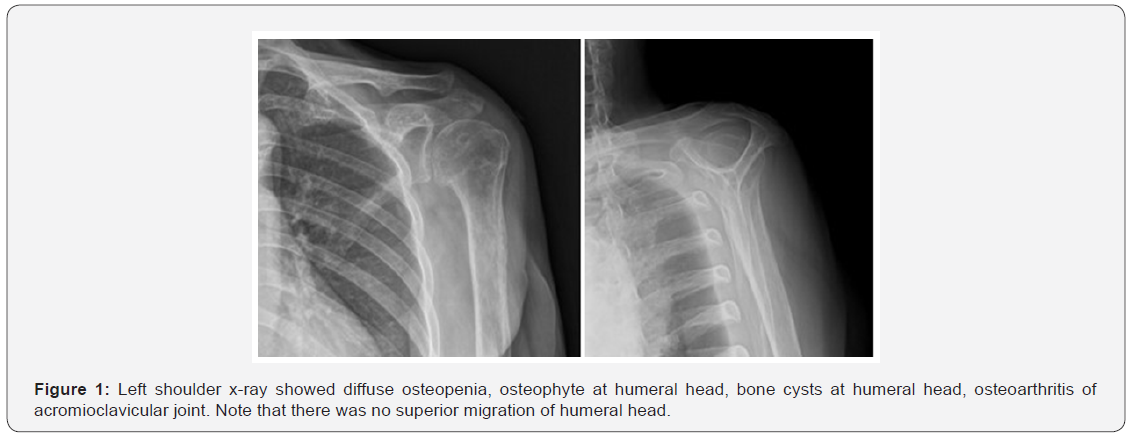

A 69-year-old right hand dominant female presented with left shoulder pain 6 months prior to admission. She had great difficulty raising her arm overhead as well as intense pain at night caused by sleeping. She sustained a minor fall from bicycle 10 months ago without significant disability. Her past medical history includes dyslipidemia and rheumatoid arthritis. Current medications are simvastatin, sulfasalazine, cyclophosphamide, methotrexate, chloroquine and folic acid. She denied alcohol drinking and tobacco use. The physical examination showed no obvious deformity or contusion. Mild tender at bicipital groove. Not tender at acromioclavicular joint. Active forward flexion was limited to 90 degrees and passive forward flexion is 160 degrees. Active arm abduction external rotation was 40 degrees, internal rotation is 30 degrees. Full passive arm abduction external rotation and internal rotation. There was positive Drop arm test, Jobe test, Lift off test, and Belly off test. The external rotation lag sign was negative. The strength test revealed 5/5 for external rotation and 2/5 for internal rotation. The x-ray of left shoulder showed mild osteoarthritis of glenohumeral joint. No superior migration of humeral head was seen (Figure 1). The MRI showed complete tear of supraspinatus with medial retraction to the level of glenohumeral joint. Suspect tear of subscapularis tendon (Figure 2).

However, we thought that the general strategy for evaluation of reparability of the rotator cuff should not be difference from normal population. For massive rotator cuff tear, the decisive factors whether to repair the rotator cuff are the tendon retraction, the fatty infiltration and the upward migration of humeral head. For this patient, although the stump of the supraspinatus tendon was retracted nearly to the glenohumeral joint level, the degree of fatty infiltration is Goutalier grade 2 and there was no proximal migration. Therefore, we considered as the reparable rotator cuff tear.

We did not perform the acromioplasty, because of the fear of sacrificing the coracoacromial ligament, thus compromising the coracoacromial arch, which will lead to more superior migration of humeral head. The acromioclavicular joint was also left untouched because the physical examination for acromioclavicular joint was negative. The Laine classification of rheumatoid arthritis of glenohumeral joint has 3 stages based on clinical and radiographic findings [3]. From clinical and x-ray findings, our patient was classified in stage 2. The reverse total shoulder arthroplasty would be better option if the patient has more severe arthritic change of the glenohumeral joint which refers to Laine classification stage 3.